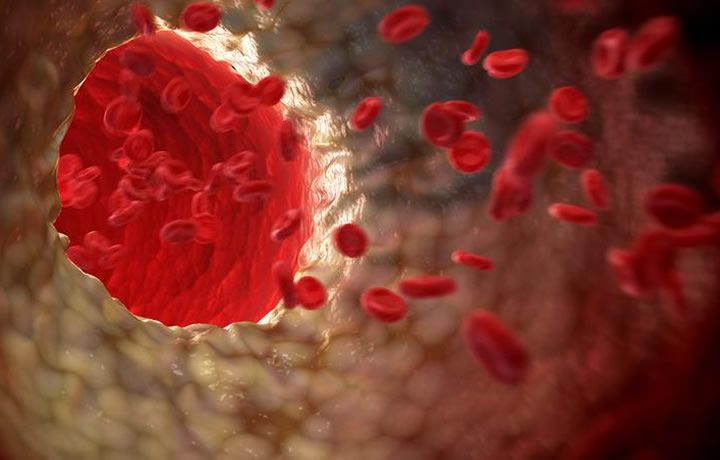

El ecógrafo vascular en tres dimensiones permite evaluar las placas de colesterol que provocan las obstrucciones que están detrás de la mayoría de infartos e ictus

Concretamente, se trata de una técnica de imagen no invasiva que explora las arterias superficiales de nuestro cuerpo, evaluando desde la presencia de las primeras alteraciones en la pared de nuestros vasos, hasta fases avanzadas de la enfermedad aterosclerótica. “Consiste en conocer cómo han impactado los diferentes factores en la salud de las arterias. Así podemos saber realmente qué pacientes tenemos que tratar y en cuáles de ellos tendríamos que utilizar tratamiento farmacológico”, señala el profesional de HM CIEC.

Por lo tanto, según incide el doctor Castellano, esta nueva tecnología hace que los especialistas estén al tanto del verdadero efecto individual que está teniendo en el organismo la exposición a factores de riesgo cardiovasculares, conocidos o no, y les permitecuantificar el riesgo real que tiene un paciente de presentar un evento cardiovascular serio, como el riesgo de desarrollar infarto de miocardio o un ictus cerebral, más allá del riesgo estimado por las escalas convencionales.

El funcionamiento de un estudio 3D vascular se realiza con una sonda específica que proporciona una imagen de los vasos en tan sólo unos segundos, simplificando el estudio de los pacientes. Además, el software de análisis ofrece muchas posibilidades. "Si se detecta aterosclerosis en las arterias, el 3D nos permite evaluar su extensión, severidad y características desde todos los ejes del espacio, dando una información más completa que la que hasta ahora obteníamos con un estudio 2D convencional”, indica el doctor.El funcionamiento de la ecografía vascular 3D ofrece una ventaja sustancial, más allá de una mejor evaluación de la ateroesclerosis, y es que este tipo de ecografía es una exploración que se puede hacer sobre la marcha, no necesita preparación, y no radia al paciente.